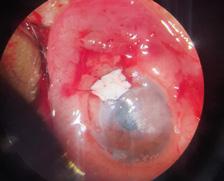

La queratitis ulcerativa periférica (QUP) es una lesión inflamatoria y destructiva del estroma y epitelio corneal yuxtalimbar que lleva a un adelgazamiento progresivo de la córnea. En su etiopatogenia están involucrados desórdenes inmunológicos favorecidos por la vasculatura perilimbar. Muchas veces cursa con escasa sintomatología, por lo que puede llegar a la perforación sin que el paciente sea consciente de ello.

La QUP puede aparecer de forma aislada o estar asociada a una enfermedad sistémica, siendo los síndromes vasculíticos los más frecuentes.

En estos casos, la QUP puede ser la primera manifestación de la enfermedad sistémica siendo la afectación ocular un signo de mal pronóstico ya que expresa actividad de la enfermedad.

La granulomatosis con poliangeitis asociada a ANCA C+ (exenfermedad de Wegener) es una vasculitis granulomatosa necrotizante sistémica, potencialmente letal, que puede afectar los tejidos oculares. En su manejo, son fundamentales el diagnóstico precoz y un tratamiento adecuado.

Paciente masculino de 48 años de edad se presenta en la guardia oftalmológica refiriendo leve dolor y molestias en el ojo izquierdo de aproximadamente 1 mes de evolución. A la anamnesis dirigida, el paciente menciona como antecedente: anemia y nefropatía en estudio.

AVMC: OD: 10/10

OI: 2/10

Bomicroscopia:

OD: inyección conjuntival mixta, úlcera corneal periférica con forma de media luna de horas 7 a 11.

OI: inyección conjuntival mixta, úlcera periférica de horas 12 a 5, con perforación a horas 3, protrusión de iris.

FO: sin particularidades en AO.

Se realiza interconsulta con reumatología y se decide intervención quirúrgica urgente de reparación primaria con parche escleral y recubrimiento conjuntival en OI, y solo recubrimiento conjuntival en OD, que se realiza el mismo día.

Luego de la cirugía, se inicia tratamiento sistémico con meprednisona 40mg/día, vía oral. El paciente presenta buena evolución a las 24 horas de postoperatorio.

En los exámenes de laboratorio solicitados por reumatología, el paciente presenta anemia, proteinuria, microhematuria, ANCA C+, diagnosticándose granulomatosis con poliangeitis asociada a ANCA C+. A los 10 días, el paciente presenta nueva úlcera corneal periférica inferior en OD, por lo que reumatología indica pulsos de metilprednisolona y posteriormente tratamiento inmunosupresor con ciclofosfamida. En los días siguientes evoluciona de forma desfavorable presentado adelgazamiento corneal periférico en AO. Se interviene nuevamente al paciente realizando recubrimiento con membrana amniótica bilateral.

En los controles presenta una evolución favorable con membrana amniótica aplicada que se reabsorbe a los 10 días –aproximadamente– en ambos ojos. Se observa franca mejoría de la superficie, transparencia, espesor e inflamación corneal.

Al mes de la última cirugía, el paciente continúa con enfermedad inactiva, asintomático y córnea en condiciones estables. Se realiza seguimiento por reumatología con tratamiento inmunosupresor mediante pulsos de ciclofosfamida.